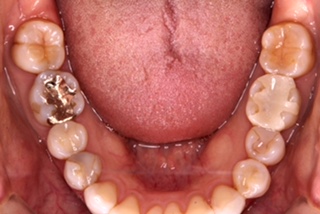

今回の治療は、右(この写真では左)の1番奥の金属、

奥から3番目はプラスチックが欠けてしまったので

セラミックにしてもらいました。

どうですか?

本来の歯と変わらないくらいに、綺麗に入れていただきました。